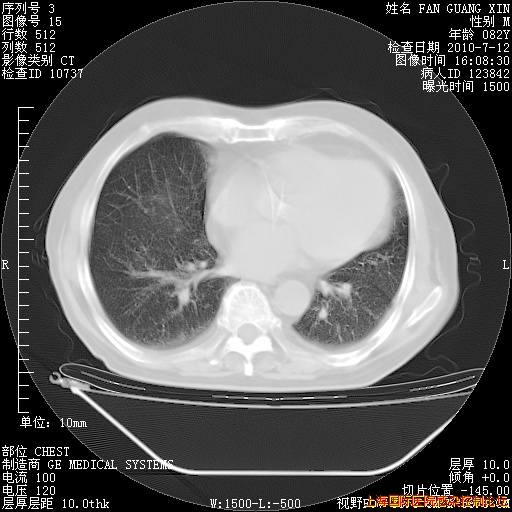

补发6月12日肺部CT肺窗

6月12日肺窗

6月12日纵膈窗

整整相隔30天的肺部CT好像有所好转啊。甲强龙减量第3天,需要观察体温。

海管,自昨日你和我通完话后,不知您岳父消化道症状有无缓解?体温怎样?阅读7.12日胸部ct,个人认为目前激素治疗是有效的,甲强龙减量是适宜的。因在抗痨治疗,需密切观察肝功、肾功能和血常规。不过,老年、长期住院和大量使用激素,很担心菌群失调发生